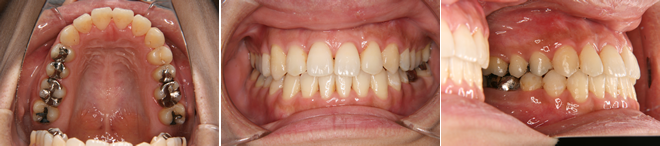

| 主訴 | 前歯のデコボコが気になる |

| 年齢・性別 | 36歳 / 女性 |

| 治療方針 | 前歯部に叢生がある切端咬合に近い軽度の反対咬合。骨格的には下顎前突。上顎の拡大により被蓋と叢生の改善を行った。 |

| 抜歯部位 | 下顎左右第3大臼歯(親知らず) |

| 使用装置 | マルチブラケット装置 |

| 治療期間 | 17か月 |

| リテーナー | 上顎インビジブル、下顎インビジブル |

| 費用 | 765,000円(税別) |